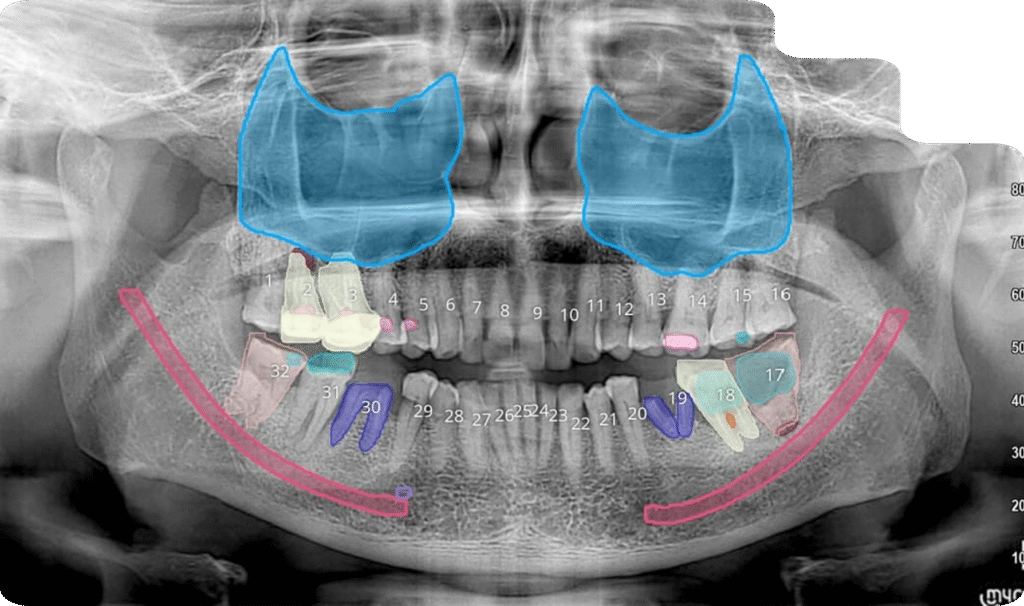

2D

2 D OPG

A panoramic radiograph is a panoramic scanning dental X-ray of the upper and lower jaw. It shows a two-dimensional view of a half-circle from ear to ear.